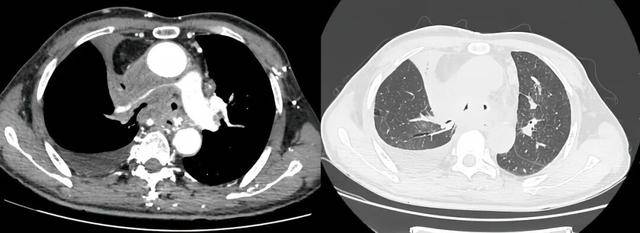

术前受压变窄的右肺动脉和中央气道